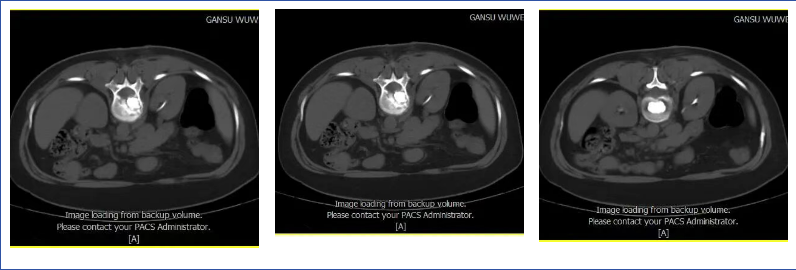

患者术前磁共振检查影像学表现:

患者术前的磁共振检查结果提示:L1椎体病变,结合病史考虑为转移癌。影像学评估提示L1椎体高信号表现,椎体高度未发生塌陷表现,椎管内容物无受压表现。患者临床腰椎功能活动受限,疼痛明显,相关生命体征平稳。

结合患者影像学检查和临床表现,认为患者存在L1病变椎体成形术的适应症,完善相关检查及术前准备后,予以患者CT引导下的椎体成形术。